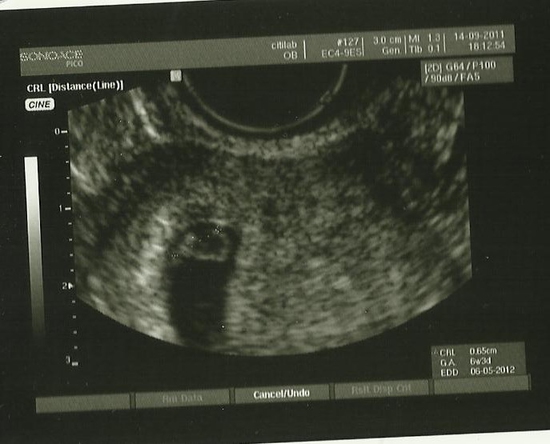

привет,на узи идут на 7 день и на 9 потом 12 затем по назначению,как развиваеться все на яичниках,я еще на 21 день ходила.

Смысла идти нет на 6ДЦ... Лучше пойти на 9-12ДЦ... Можно посмотреть и ДФ и эндометрий!

Мне назначали на 7ДЦ. Смотрели прошла функциональная киста, или образовалась новая, или осталась старая!

ну вообще по идее на узи надо на8-10дц....если у тебя не пооучается и потрм узистка не работает,то лучше завтра...

Яичники в принципе посмотреть можно. Хотя лучше было бы попозже. Хотя- опять таки- смотря какой длинны цикл. если короткий- то даже хорошо, что так рано.